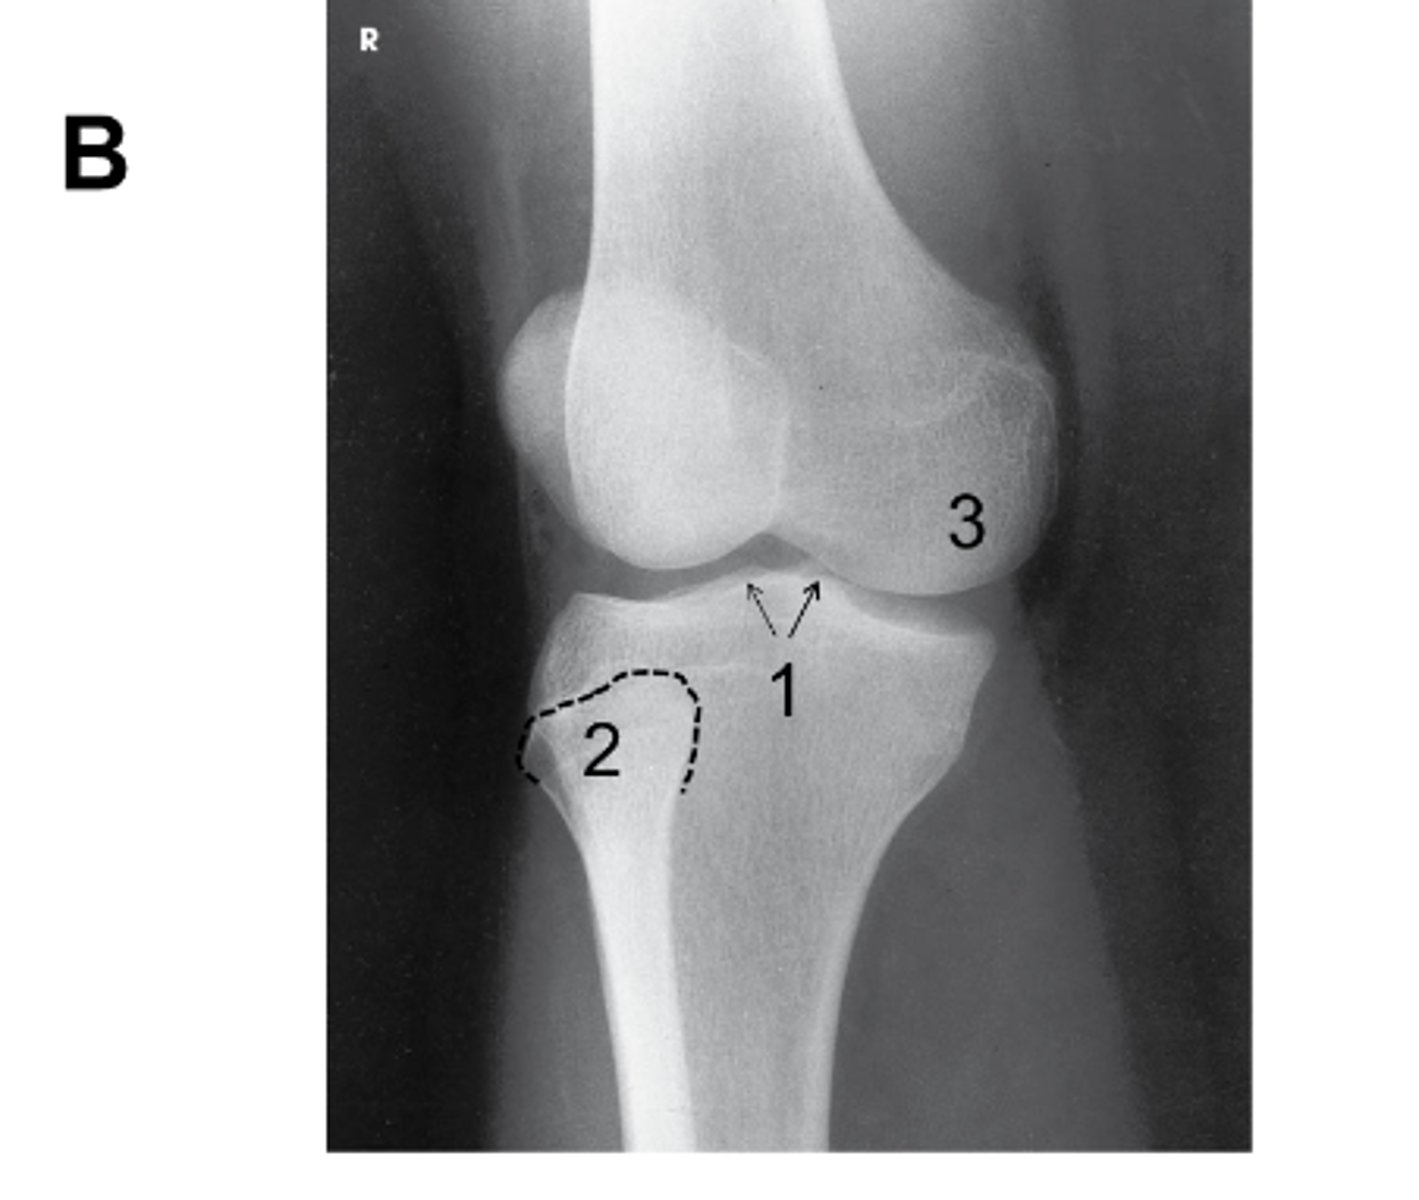

What anatomy is labeled with the letter B in the image below?

Proximal tibiofibular joint

What lower limb position is required to obtain the image below?

45-degree medial rotation

What anatomy is best demonstrated on an AP oblique knee, medial rotation?

Prox tib/fib joint, head of the fibula, and lateral condyles

Identify the projection. (Be prepared to critique for positioning on the quiz)

AP Oblique Knee, medial rotation

Is there an angle on the CR in this projection? (Be prepared to explain how you know on the quiz)

Yes